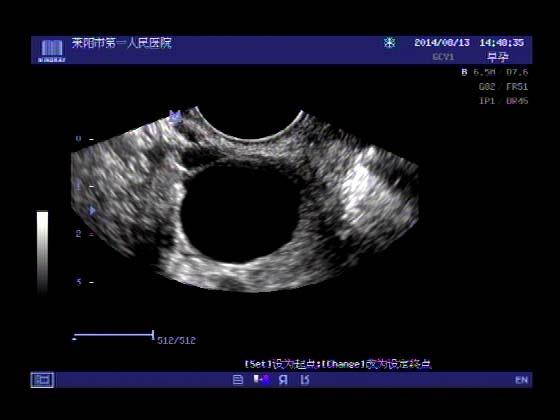

超声入门贴341:宫外孕(阴超的魅力)

女,32岁,停经15天,

一周前在上极医院检查:化验尿HCG阳性,血HCG400多,超声检查问见明显孕囊,让随访。

看见卵黄囊啦~孕囊型的吧?

还能看到卵黄囊,真不错